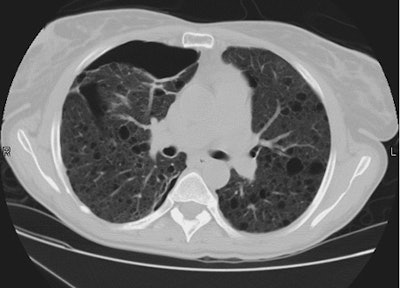

Diaphragmatic Rupture:

The patient shown below presented following a motor vehicle accident. The CXR demonstrated abnormal opacification over the lower left hemithorax which was very suggestive of a diaphragmatic injury.

CT imaging confirmed the presence of a diaphragmatic tear. The diaphragm was discontinuous, the stomach and bowel loops can be identified in the thoracic cavity, and there was also a dependent visera sign.